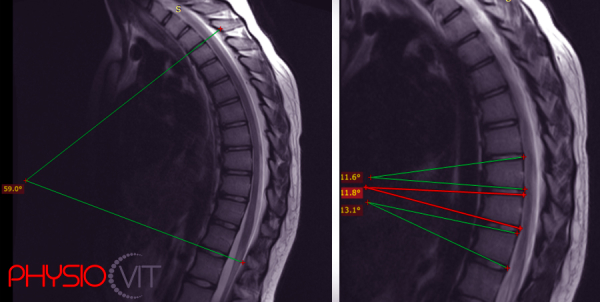

Képzelje el a gerincét, mint egy rugalmas, hajlékony fát, amely tartja a teste egészét, és minden mozdulatában együtt dolgozik Önnel. Most gondolja el, ha ennek a fának az egyik oldala jobban nő, vagy az egyik ága oldalra hajlik és csavarodik – ez történik a gerincferdülés esetén. Az érintett csigolyák mozgékonysága legtöbbször lényegesen lecsökkent, olyannyira, hogy a csigolyaoszlop aktív kiegyenesítése már nem lehetséges. Az oldalirányú görbülethez legtöbbször társul a csigolya elfordulása (torzió) is, aminek következtében a háti szakaszon bordapúp, az ágyéki szakaszon ágyéki púp alakul ki. De mit is jelent ez pontosan a mindennapokban, és mit tehet ellene? Nézzük meg együtt! Hogyan alakul ki a gerincferdülés? A gerincferdülés kialakulásának kiváltó okai sokfélék lehetnek, kezdve ideg-izom problémáktól, fejlődési zavarokon át egészen a…